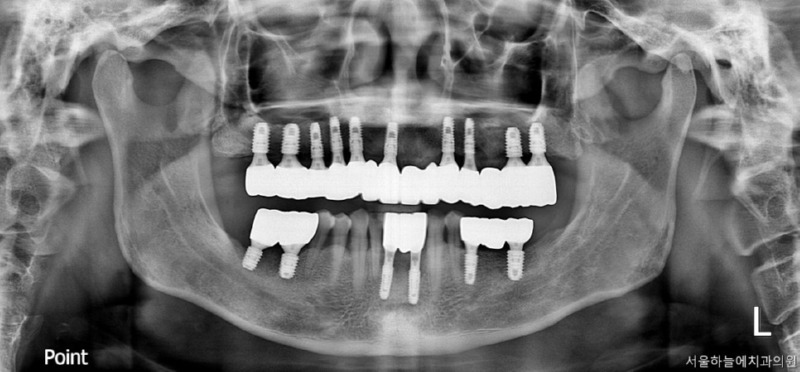

수술 후 6개월 후 보철완료

치료 전 / 치료 후

전신질환이 있어도, 기준은 분명합니다

당뇨·고혈압이 있다고 해서

임플란트를 포기하실 필요는 없습니다.